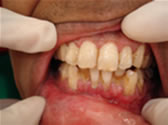

Early symptoms of gum disease include gum bleeding without pain. Pain is a symptom of more advanced gum disease as the loss of bone around the teeth leads to the formation of gum pockets. Bacteria in these pockets cause gum infection, swelling, pain, and further bone destruction. Advanced gum disease can cause loss of otherwise healthy teeth.

It is a progressive inflammatory disease of the gums and the surrounding tissue around the teeth. It is commonly known as gum disease and was referred to as pyorrhea in the old days. It is estimated that up to 80% of the population above the age of 40 may suffer from this disease with the severity varying drastically from one person to another. Periodontitis is the number one cause of tooth loss after the age of 40.

If you notice any of the following signs of gum disease, schedule an appointment immediately:

Fig. 3 |